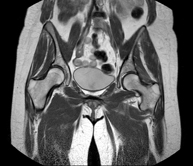

Exploració per a l'estudi de lesions a tendons, músculs i articulacions coxofemorals. Permet identificar de manera precoç l'artrosi de maluc. Resulta molt útil per detectar les bursitis i l'osteopatia dinàmica de pubis, freqüent en esportistes. La durada aproximada és de 20 minuts. No utilitza radiació ionitzant. - RM de Sacroilíaques